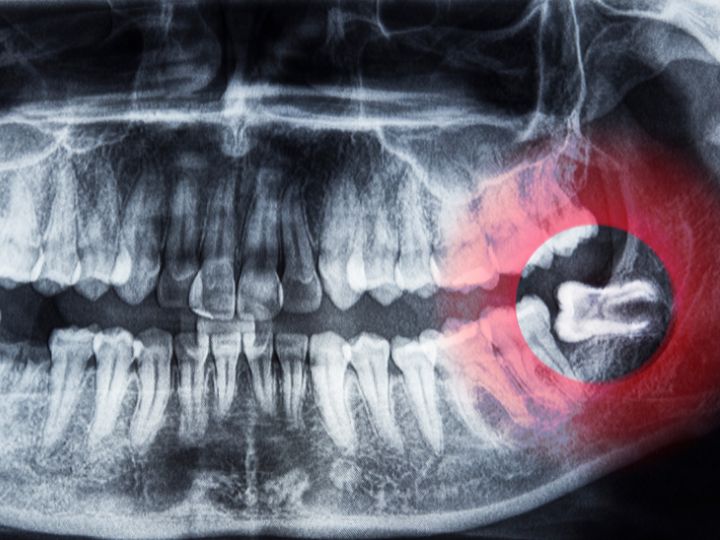

Posteriormente, se hace uso de las radiografías. Estas son herramientas que nos ayudan a diagnosticar la presencia de las muelas del juicio, ya que proporcionan imágenes detalladas de la mandíbula y las estructuras circundantes. Los tipos comunes de radiografías utilizadas incluyen radiografías panorámicas y radiografías periapicales. Estas imágenes permiten evaluar la posición, el tamaño, la forma y la orientación de las muelas del juicio, así como identificar cualquier impactación, anomalía o complicación potencial.

- Impactación: Es uno de los problemas más comunes causados por las muelas del juicio. Ocurre cuando una o más muelas no pueden emerger completamente a través de la encía y quedan atrapadas parcial o completamente dentro del hueso maxilar o mandibular. Esto puede deberse a una variedad de razones, como la posición anormal de la muela o la obstrucción por otros dientes. La impactación puede provocar dolor, inflamación e infección en el área afectada, y a menudo requiere tratamiento dental para su extracción.

- Falta de espacio en la mandíbula: Otro problema frecuente asociado con las muelas del juicio es la falta de espacio en la mandíbula para que las muelas erupcionen correctamente. Esto puede deberse a la estructura ósea subyacente o a la presencia de otros dientes en la misma área. Cuando no hay suficiente espacio para que las muelas del juicio se desarrollen adecuadamente, pueden quedar impactadas o crecer en ángulos anormales.